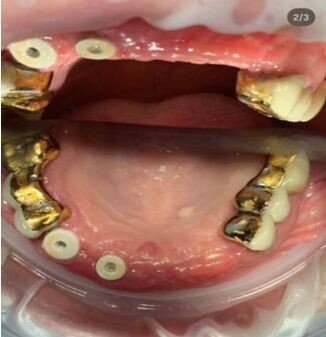

Фотогалерея